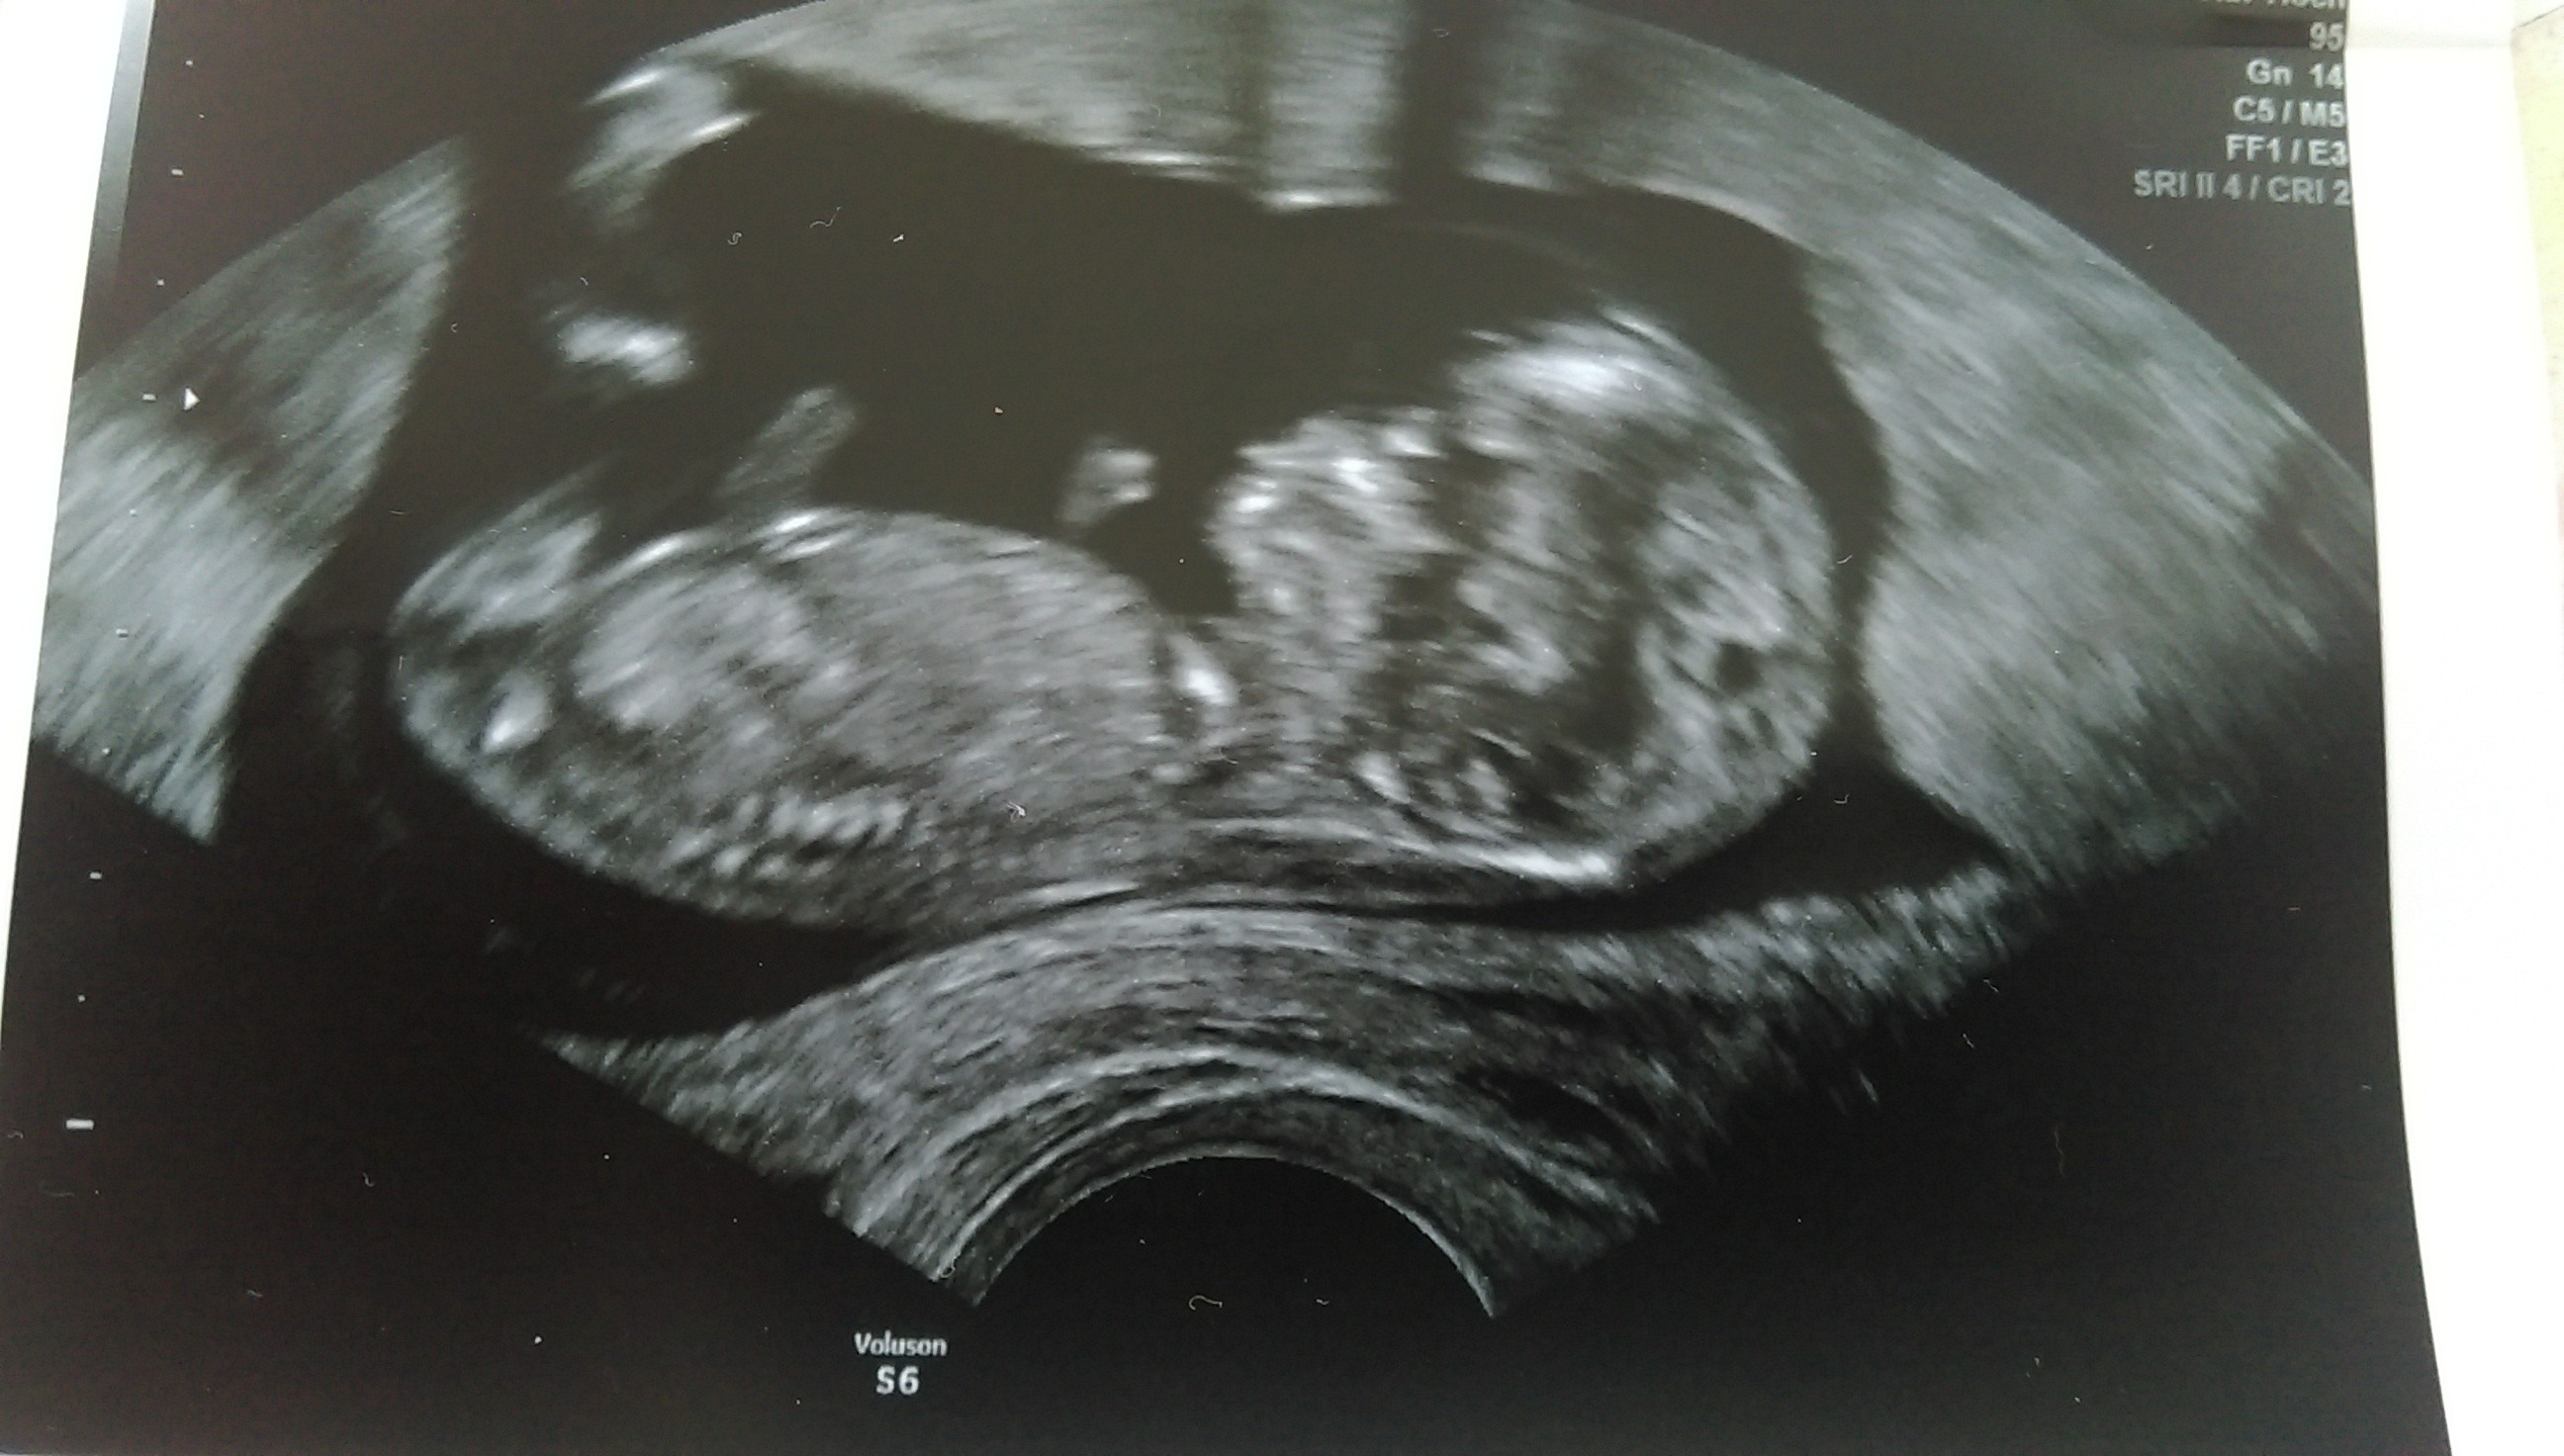

Ja też już po wizycie. Dzieciątko ma 6,1 cm - wielka ulga, że ładnie rośnie, bo ja nie rosnę... waga w najlepszym wypadku jak sprzed ciąży. Przezierność też ok. Tylko trochę podwyższone TSH, bo 2,69. Tak jak u pozostałych dzisiaj wizytujących, maleństwo było bardzo ruchliwe i trudno było zrobić zdjęcie albo zobaczyć płeć.

Jakie piękne zdjęcie! Cudne dzieciątko. Piękny prezent na dzień mamy ^^